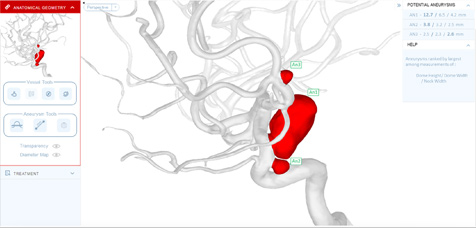

Comprehensive Aneurysm Management

SurgicalPreview®, a cloud-based computational platform, provides comprehensive cerebral aneurysm management—automating the entire workflow from initial assessment to growth monitoring and treatment planning.

SECURE AUTOMATION. SINGLE PLATFORM. HIPAA COMPLIANT.